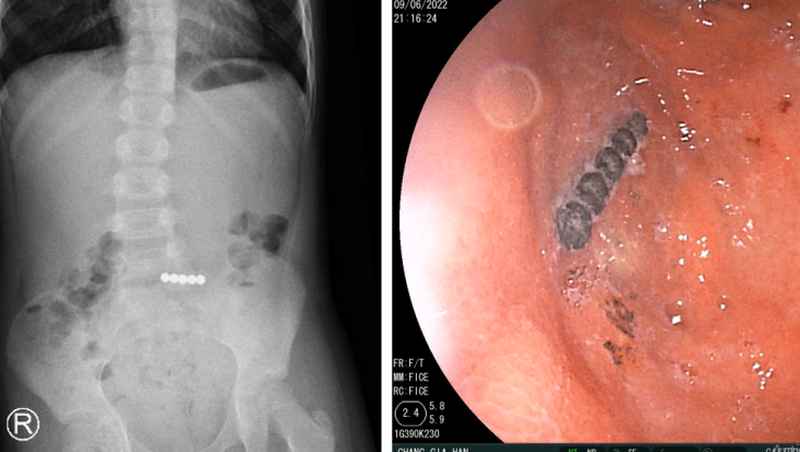

Tại bệnh viện, bệnh nhi biểu hiện đau bụng, nôn ói, hốt hoảng, được các bác sĩ hỗ trợ hô hấp thở oxy. Kết quả chụp X-quang bụng không sửa soạn phát hiện dị vật ở ruột non.

Các bác sĩ đã tiến hành hội chẩn các bác sĩ chuyên khoa tiêu hóa và phối hợp với các bác sĩ ngoại khoa tiến hành nội soi đường tiêu hóa cấp cứu và nội soi ổ bụng, đẩy dị vật từ ruột non lên dạ dày cho bác sĩ tiêu hóa nội soi gắp ra 5 viên bi nam châm dính liền nhau.